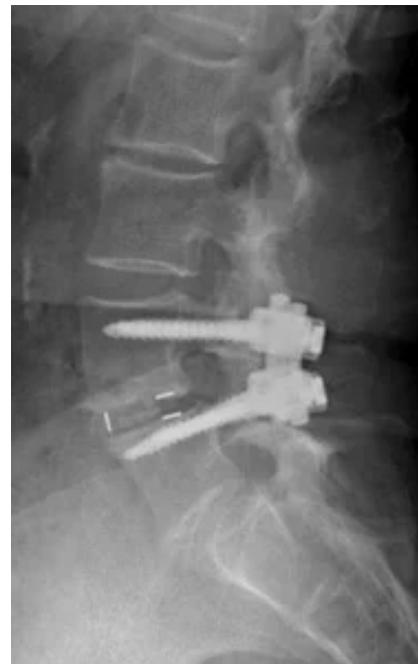

Lumbar Disc Herniation

- Significance: Very common cause of low back pain and unilateral leg pain (radiculopathy)

- Diagnosis: Made clinically and confirmed with MRI studies of lumbar spine

- Initial treatment: Nonoperative with oral medications and physical therapy for radicular leg pain

- Surgical indication: Microdiscectomy for severe pain and/or motor deficit that have failed to respond to nonoperative management

L5/S1 Disc Herniation Example: